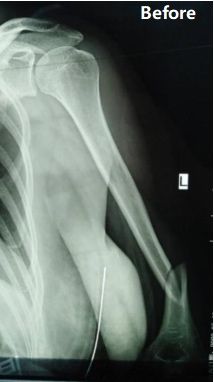

Обзор случая: у 48-летней пациентки был диагностирован перелом от средней до дистальной трети левого плеча (классификация АО: тип B1).

Хирургическая бригада выбрала минимально инвазивный пластинчатый остеосинтез (MIPO) с помощью переднего подхода с использованием орто-мостовой системы (OBS). Операция была успешно завершена в течение 90 минут, с предполагаемой потерей крови около 150 мл и длиной разреза около 8 см.